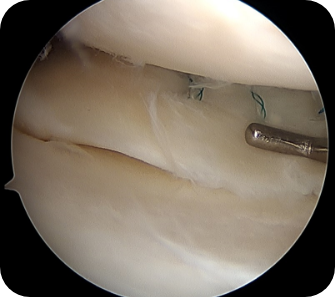

• 3) 관절경하 연골판 이식술

반월상 연골판의 심한 파열이나 원판형 연골판의 손상 등으로 인해 남아있는 연골판이 거의 없는 경우, 새로운 연골판을 이식해주는 방법입니다. 다른 사람의 기증받은 연골판을 이식하는 것으로 무릎관절 및 연골판의 크기가 비슷한 것을 처리하여 부작용이 없게 만든 후 사용하게 됩니다.

수술방법

관절내시경을 이용하여 무릎 안을 보면서 약 3~4cm 정도 절개하여 경골고평부에 구멍을 뚫고 뼈가 붙어있는 연골판을 구멍에 맞추어 다듬은 다음 넣어 고정합니다.

• ▲ 무릎 연골판 이식술 전

• ▲ 무릎 연골판 이식술 후

수술장점

새로운 연골판을 뼈와 같이 이식하기 때문에 가장 안정적인 유합을 얻을 수 있으며, 연골판을 살릴 수 없는 상태에서 가능한 유일한 방법입니다.

수술 후 관리법

이식한 뼈와 연골판이 원래의 무릎관절과 하나가 될 때까지 안정기간이 필요합니다. 전방십자인대 재건술과 거의 유사한 안정기간 및 재활기간을 요하며, 수술 후 1달 ~ 2달간의 목발, 2달간의 보조기 착용을 요하며, 이후에도 6개월까지는 달리기 등은 불가능합니다. 축구 등 구기종목으로 복귀에는 9개월에서 1년이 소요됩니다.